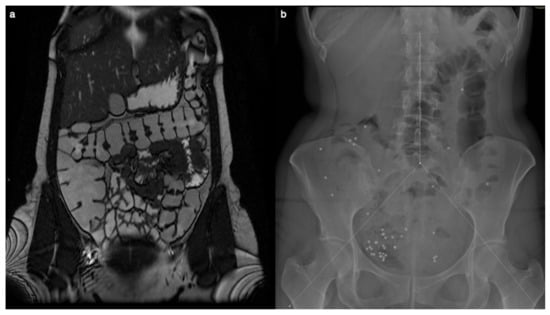

Surgery was eventually pursued because of overwhelming intestinal obstruction involving the right colon and distal ileal resection. On histological examination, the walls of both the small and large intestines exhibited mucosal atrophy, particularly notable in the cecal region, accompanied by a dense lymphocytic infiltrate (Figure 2) within the lamina propria composed of a mixture of small-sized T cells (CD3+, CD5+) and small B-lymphocytes (CD20+, CD79a+, CD5-, BCL2+, CD10-, BCL6-), the latter organized in follicles with occasional germinal centers (CD10+, BCL6+, BCL2-).

Figure 2.

Dense infiltrate was observed within the lamina propria ((a), H&E stain) composed of small CD20+ B lymphocytes organized in follicles (b) admixed with a CD3+ T cell infiltrate (c). Scalebar = 800 microns.